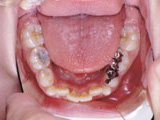

症例3:反対咬合(受け口)

治療前 治療途中 治療後